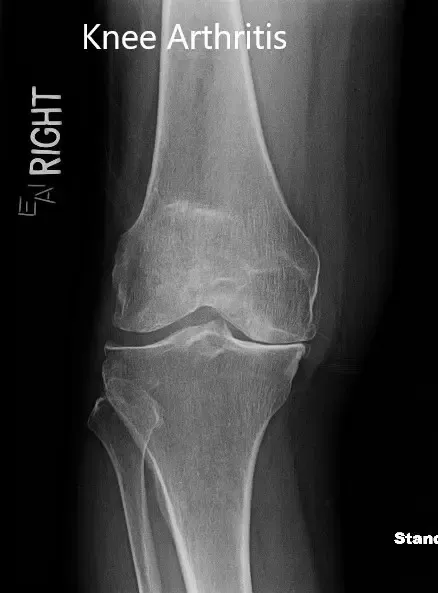

Los resultados de imagen revelaron una osteoartritis tricompartmental severa de la rodilla. Dado que su estilo de vida limita el dolor de rodilla, le recomendaron un reemplazo total de rodilla con instrumentos personalizados. Los riesgos, beneficios y alternativas se discutieron extensamente con el paciente. Él estuvo de acuerdo con el plan.

Radiografía preoperatoria que muestra la vista anteroposterior y lateral de la rodilla derecha.